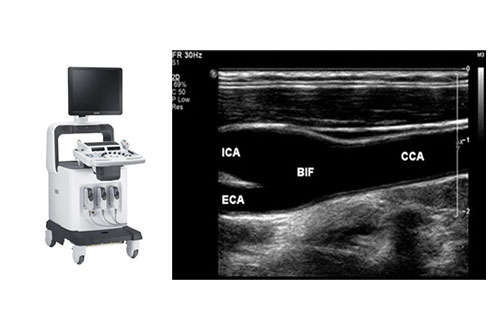

뇌졸중 위험, 미리 발견하는 현명한 선택 경동맥 초음파

수성한미병원 심뇌혈관검진센터에서는 고해상도 경동맥 초음파 장비를 통해 뇌혈관 질환의 주요 원인인

경동맥 협착과 동맥경화를 조기에 진단합니다.

간단하고 빠른 검사로 뇌졸중의 위험을 사전에 파악하고 예방할 수 있습니다.